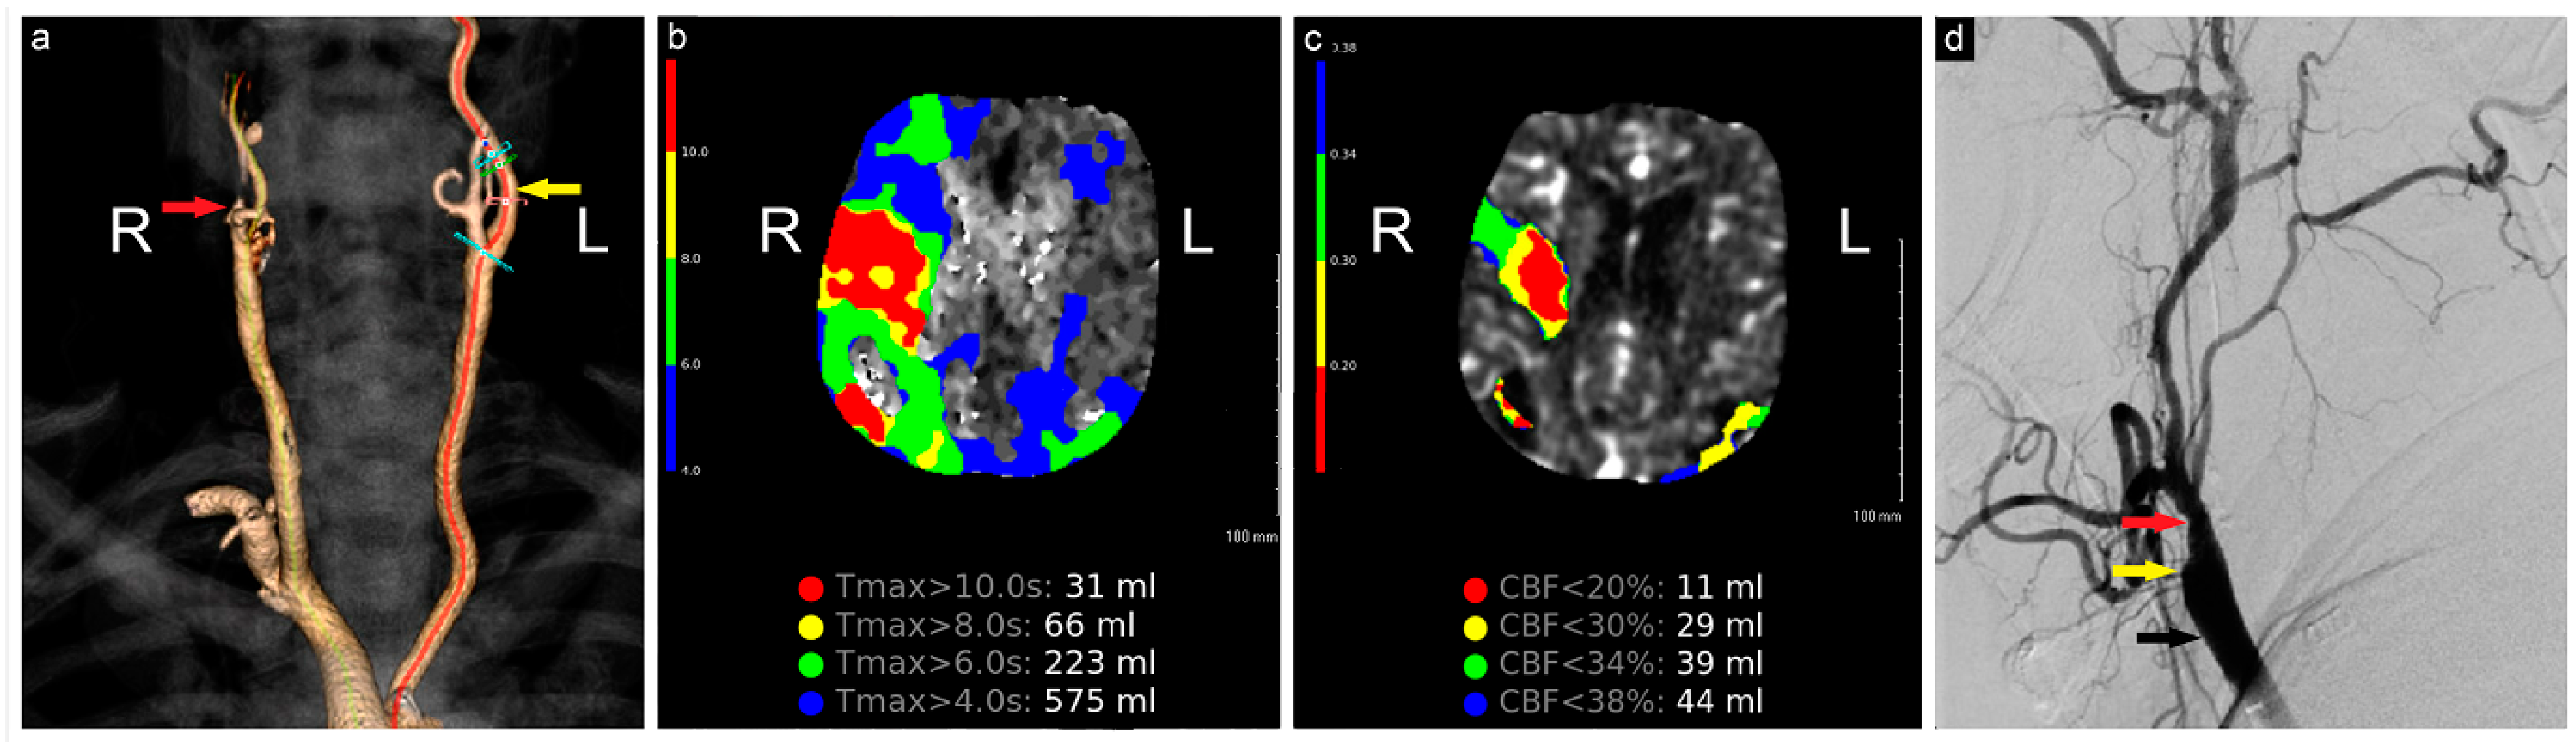

The initial computed tomography angiography (CTA) at an outside hospital showed a completely occluded right internal carotid artery (ICA). The patient was loaded with aspirin and transferred to our institution for further evaluation and treatment. On arrival, additional neuroimaging studies were conducted (Figure 1). Endovascular and open cerebrovascular services were then consulted for a possible thrombectomy and recanalization intervention.

Figure 1.

Preoperative neuroimaging. (a) CTA shows complete occlusion of the right ICA; (b) computed tomography perfusion study shows a large region of Tmax > 6 s (time to maximum of the tissue residue function) measuring 223 mL, primarily involving the right middle cerebral artery territory, (c) with a smaller region of CBF< 30% measuring 29 mL in the same territory. The mismatch volume and ratio were 194 mL and 7.7, respectively, with a hypoperfusion index of 0.1; (d) angiogram shows complete occlusion of the right ICA (yellow arrow), patent ECA (red arrow), and CCA (black arrow). R: Right, L: Left, CBF: Cerebral Blood Flow.